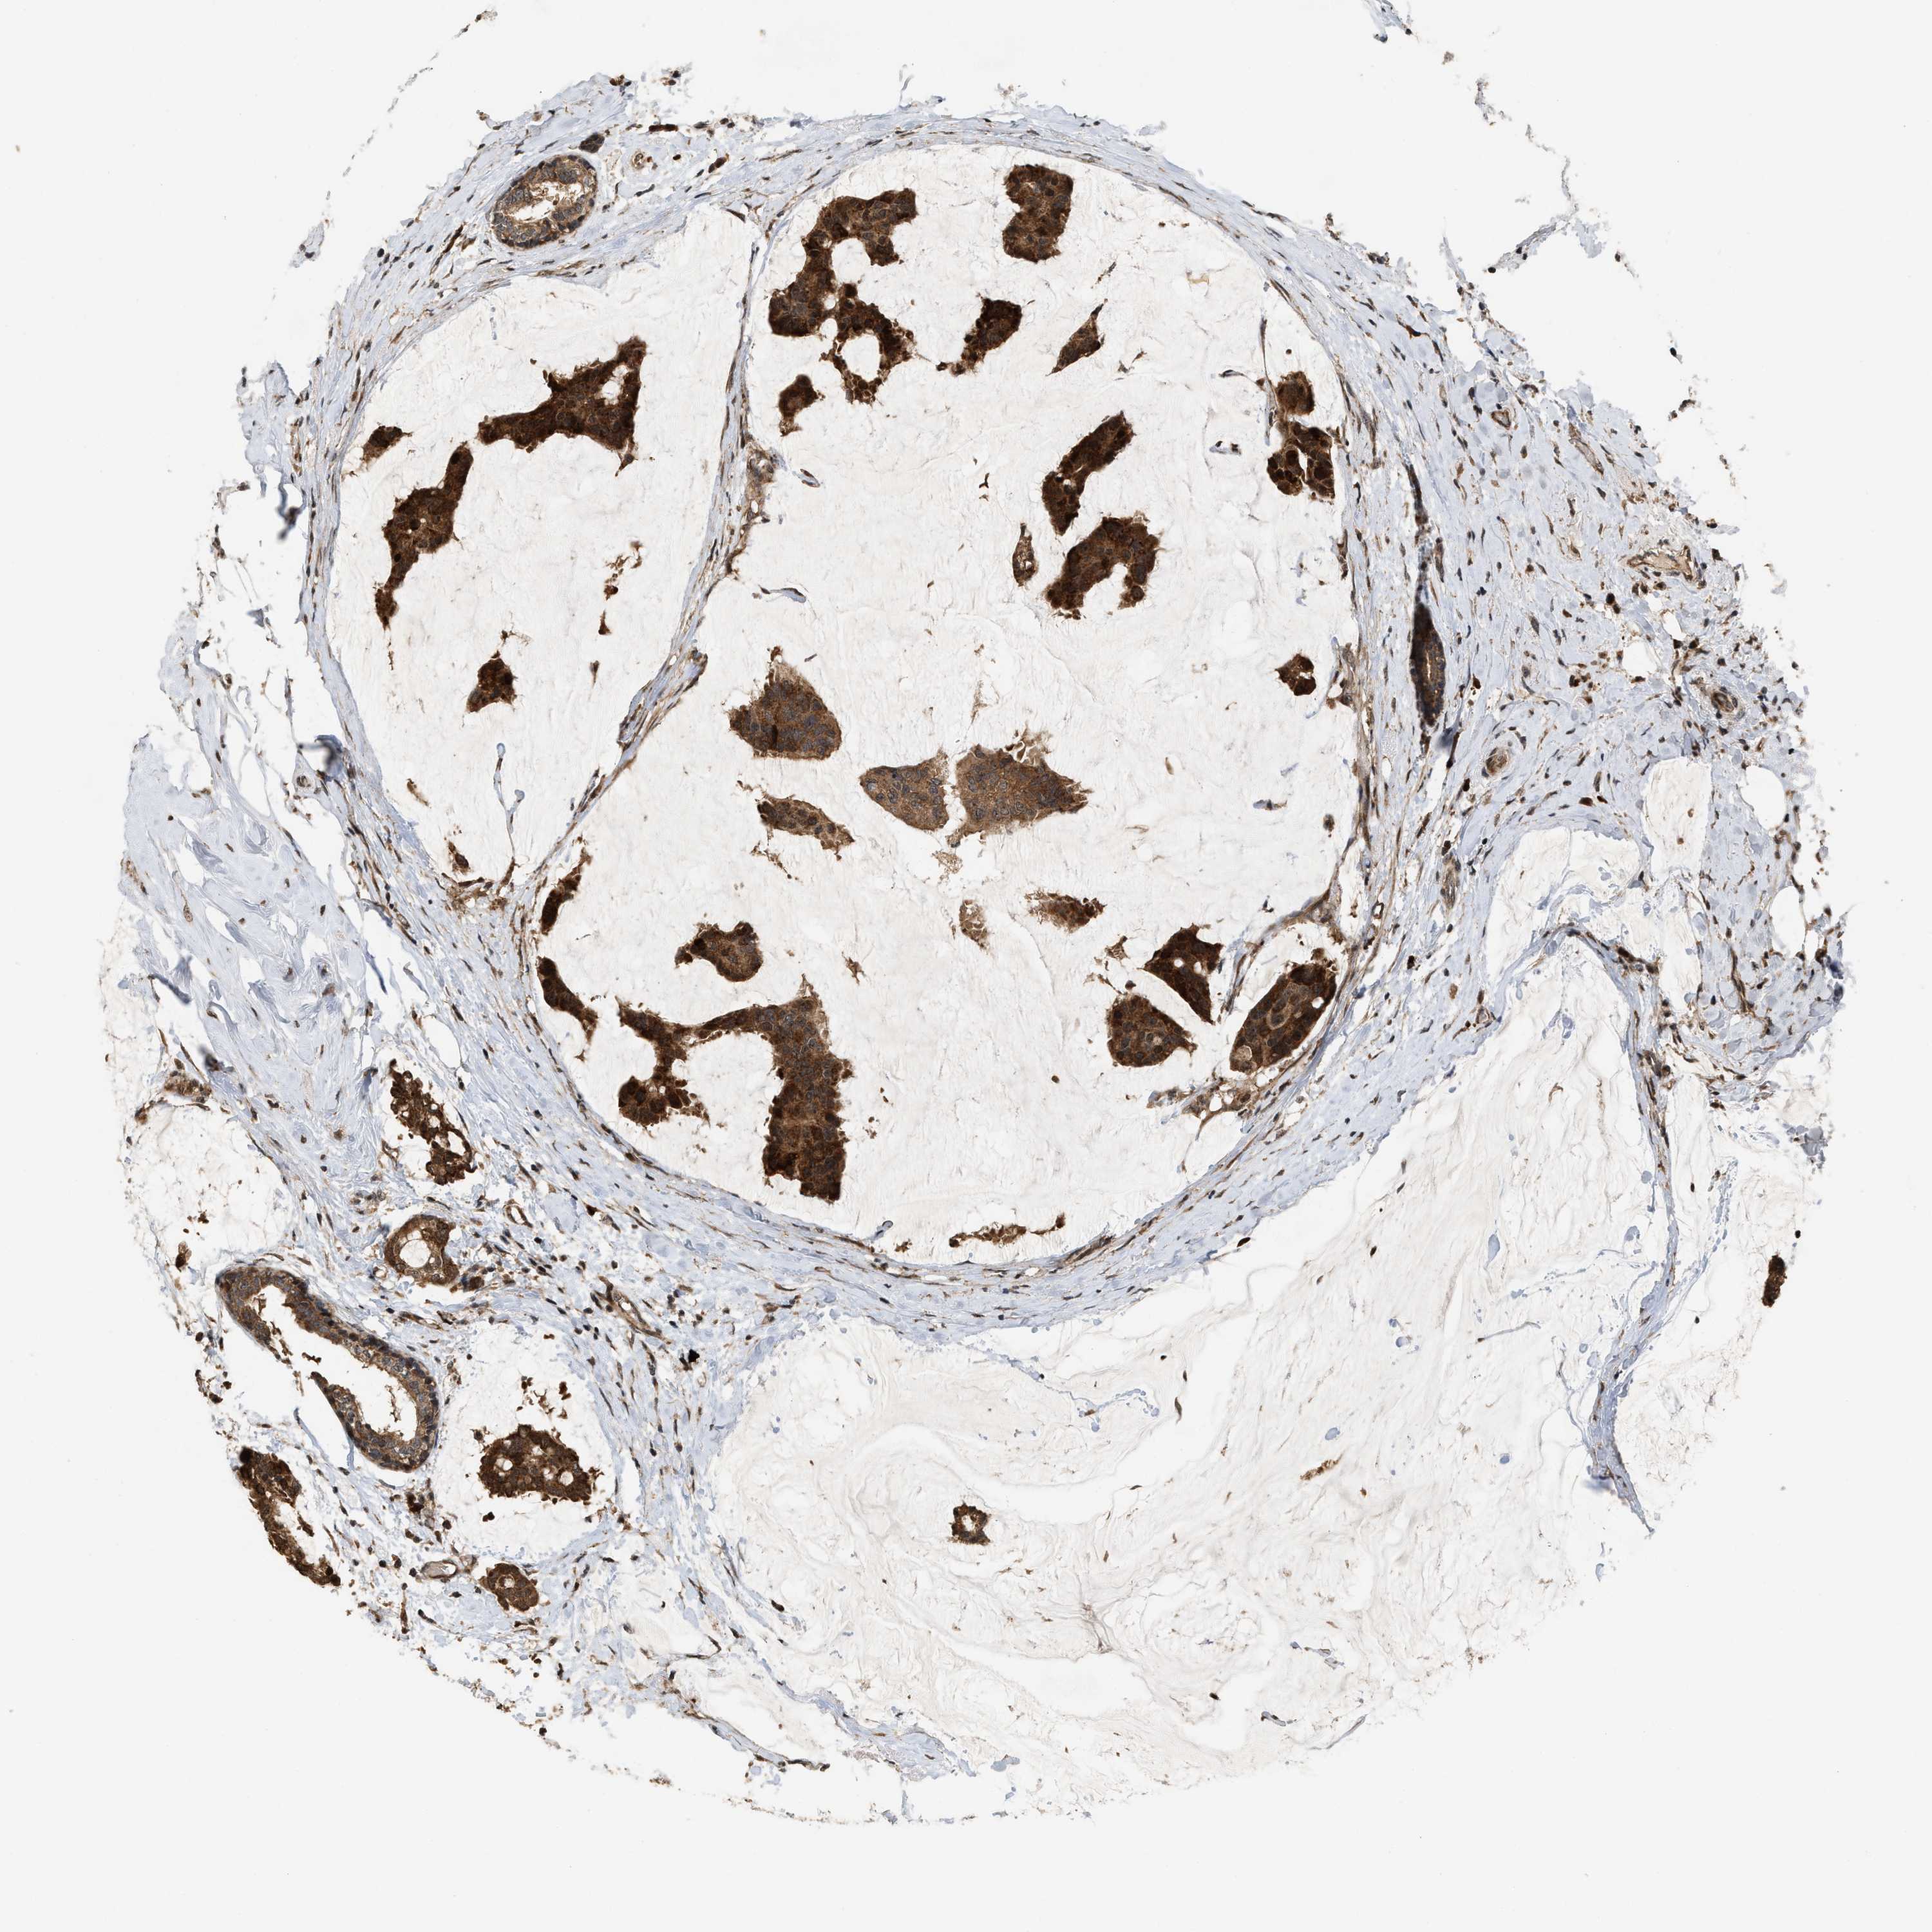

CANCER BREAST CANCER Show tissue menu

BRCA TCGA BRCA VALIDATION PROTEIN EXPRESSION

Breast cancer

Human cancer

ELP2 is not prognostic in Breast Invasive Carcinoma (TCGA)